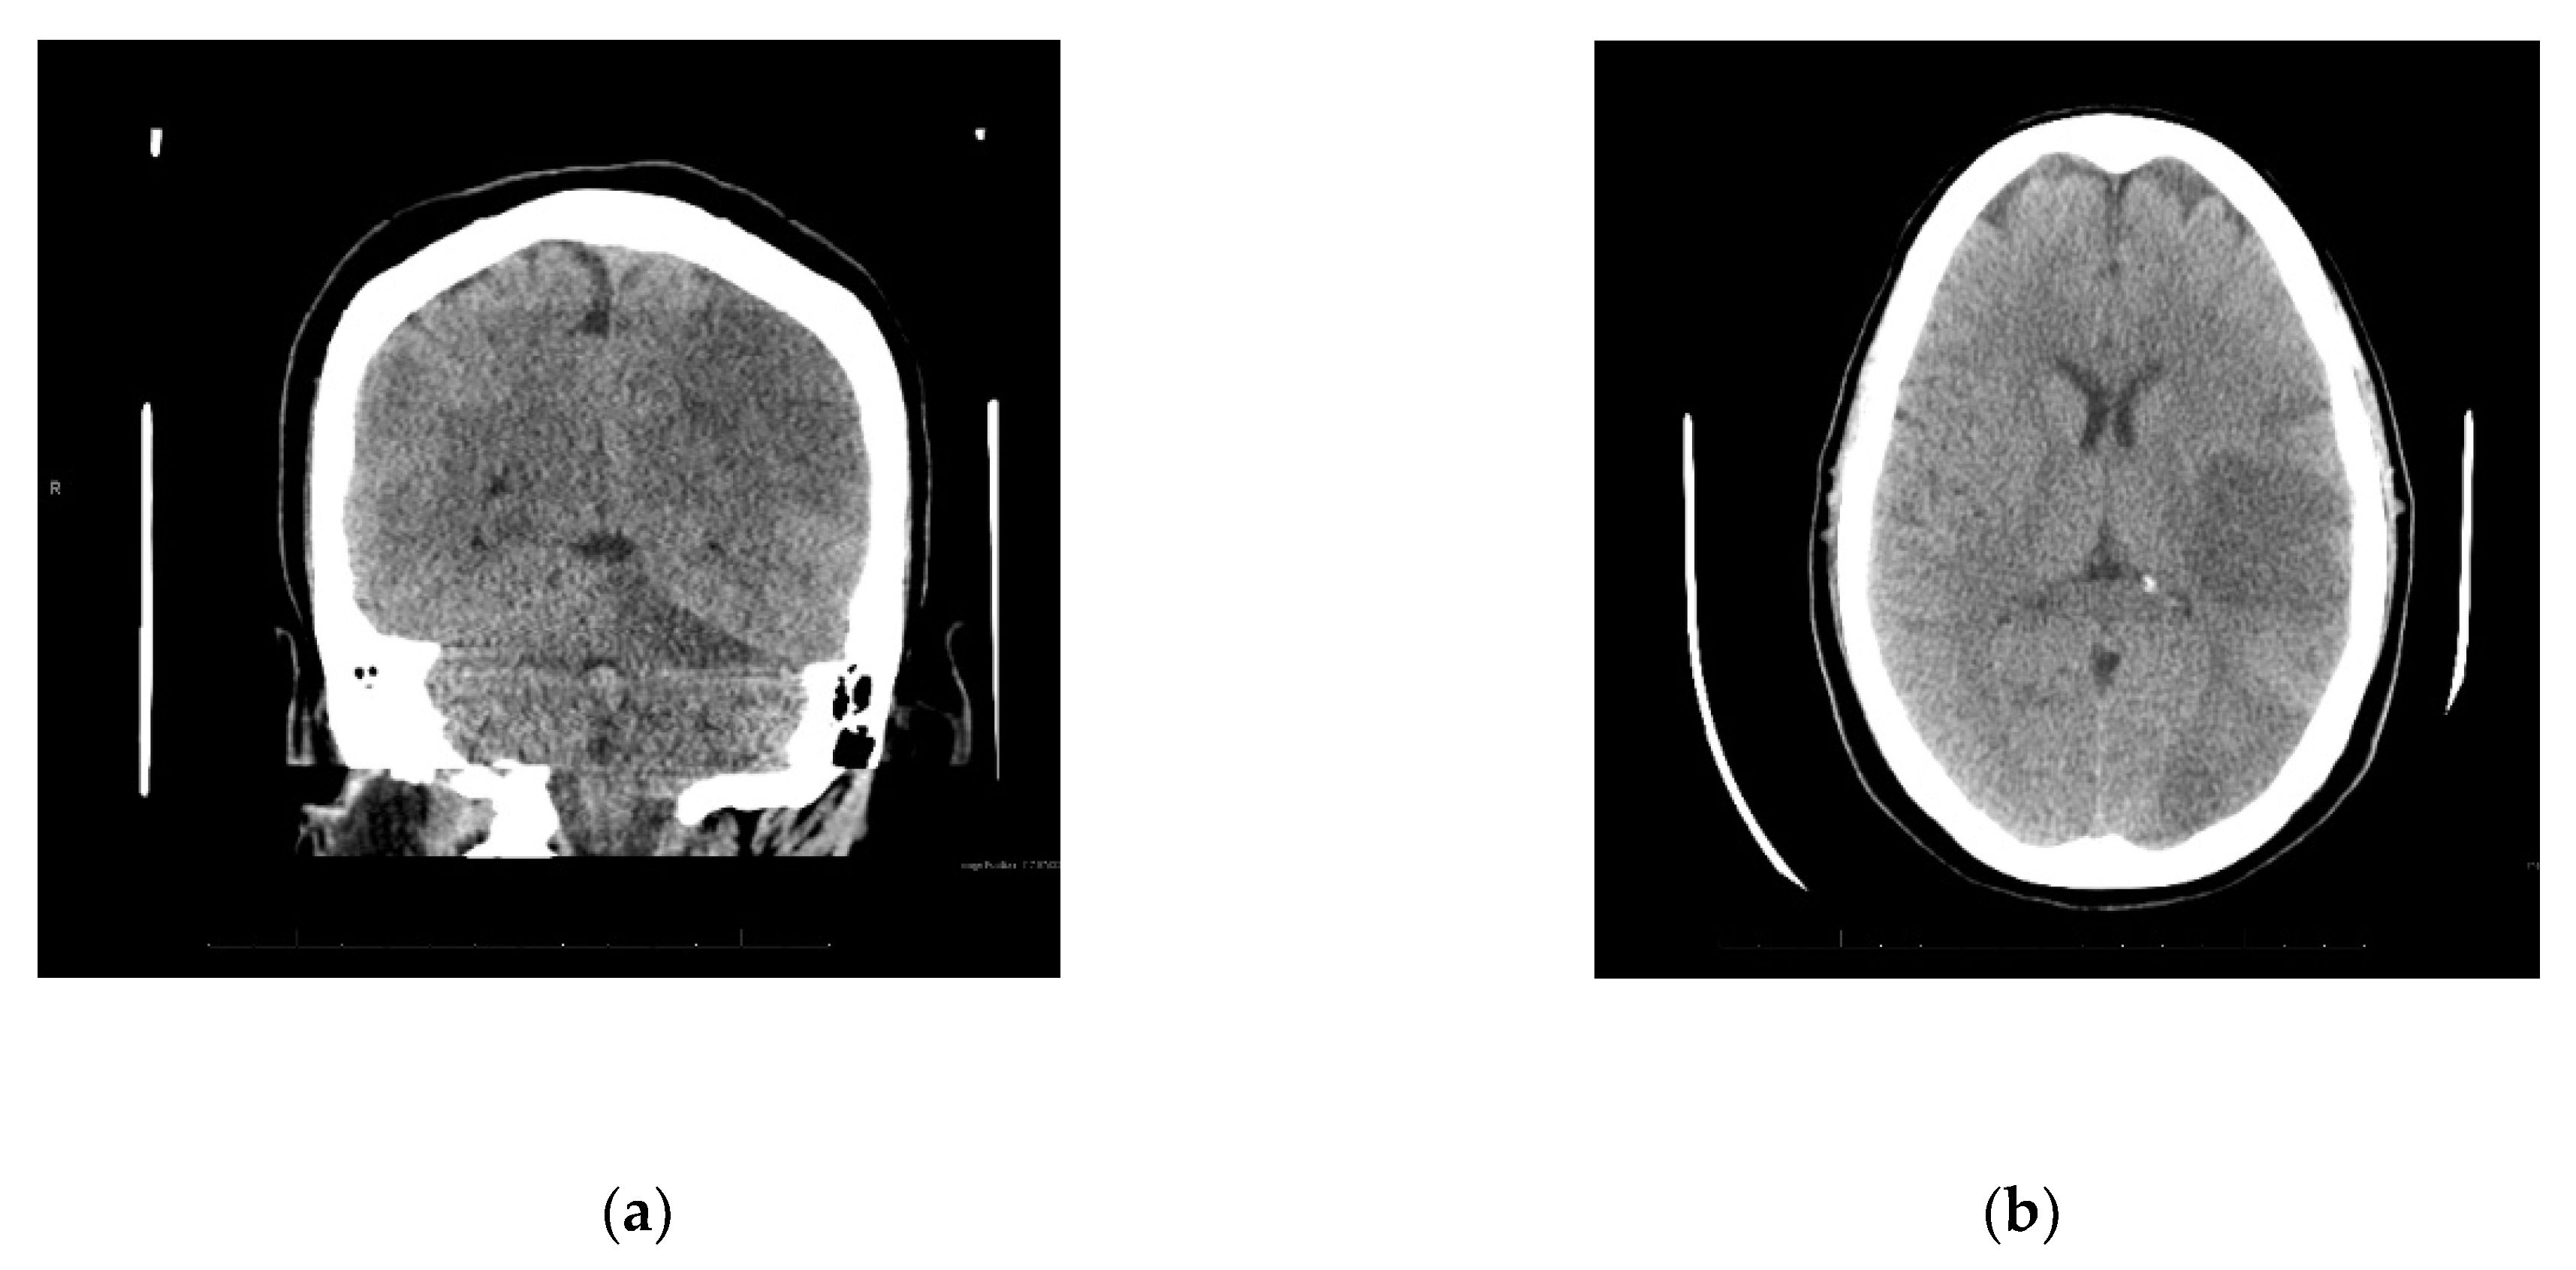

Upon arrival to the new facility, the patient was admitted to the Intensive Care Unit (ICU) and started on a Bumex drip and had a 2D-echocardiogram performed. The echocardiogram demonstrated a positive bubble study in the left atrium, suggesting a patent foramen ovale (PFO), severe pulmonary hypertension with a right ventricular mild dilation and reduced function. During the first three days of admission to the new hospital, the patient developed thrombosis of her right radial artery requiring a radial thrombectomy; she required a transfusion of one unit of packed red blood cells and one unit of platelets, plasmapheresis due to a possible TTP, and a Nicardipine (Cardene) drip. Dry gangrene in the distal right thumb developed due to a right radial artery thrombus (Figure 1b). The patient also demonstrated decreased responsiveness while on sedation vacation. A CT of the brain taken during this time reported multifocal acute infarcts involving the bilateral cerebral hemispheres and the left cerebellar hemisphere, given involvement of multiple vascular territories (Figure 2). A CT arteriogram of the brain and neck with IV contrast demonstrated an incomplete occlusive filling defect of the proximal internal jugular vein, raising concern for a partial thrombosis.

Figure 2.

(a) Diffuse infarcts; (b) Temporal and occipital lobe infarcts.

Four weeks after initial presentation to the emergency department, a neurocritical care evaluation reported the left posterior middle cerebral (MCA) and posterior cerebral (PCA) arteries, and right PCA and left superior cerebellar artery (SCA) infarcts. The report suggested severe encephalopathy. A CT angiogram of the head and neck showed no large vessel occlusion or significant steno-occlusive disease. Venous dopplers of the lower extremities was positive for a right external iliac vein non-occlusive deep vein thrombosis (DVT) for which she received an IVC filter. The patient had developed flaccid quadriplegia during hospitalization over the past month. She remains sedated on propofol and fentanyl and is poorly responsive when sedation is held.